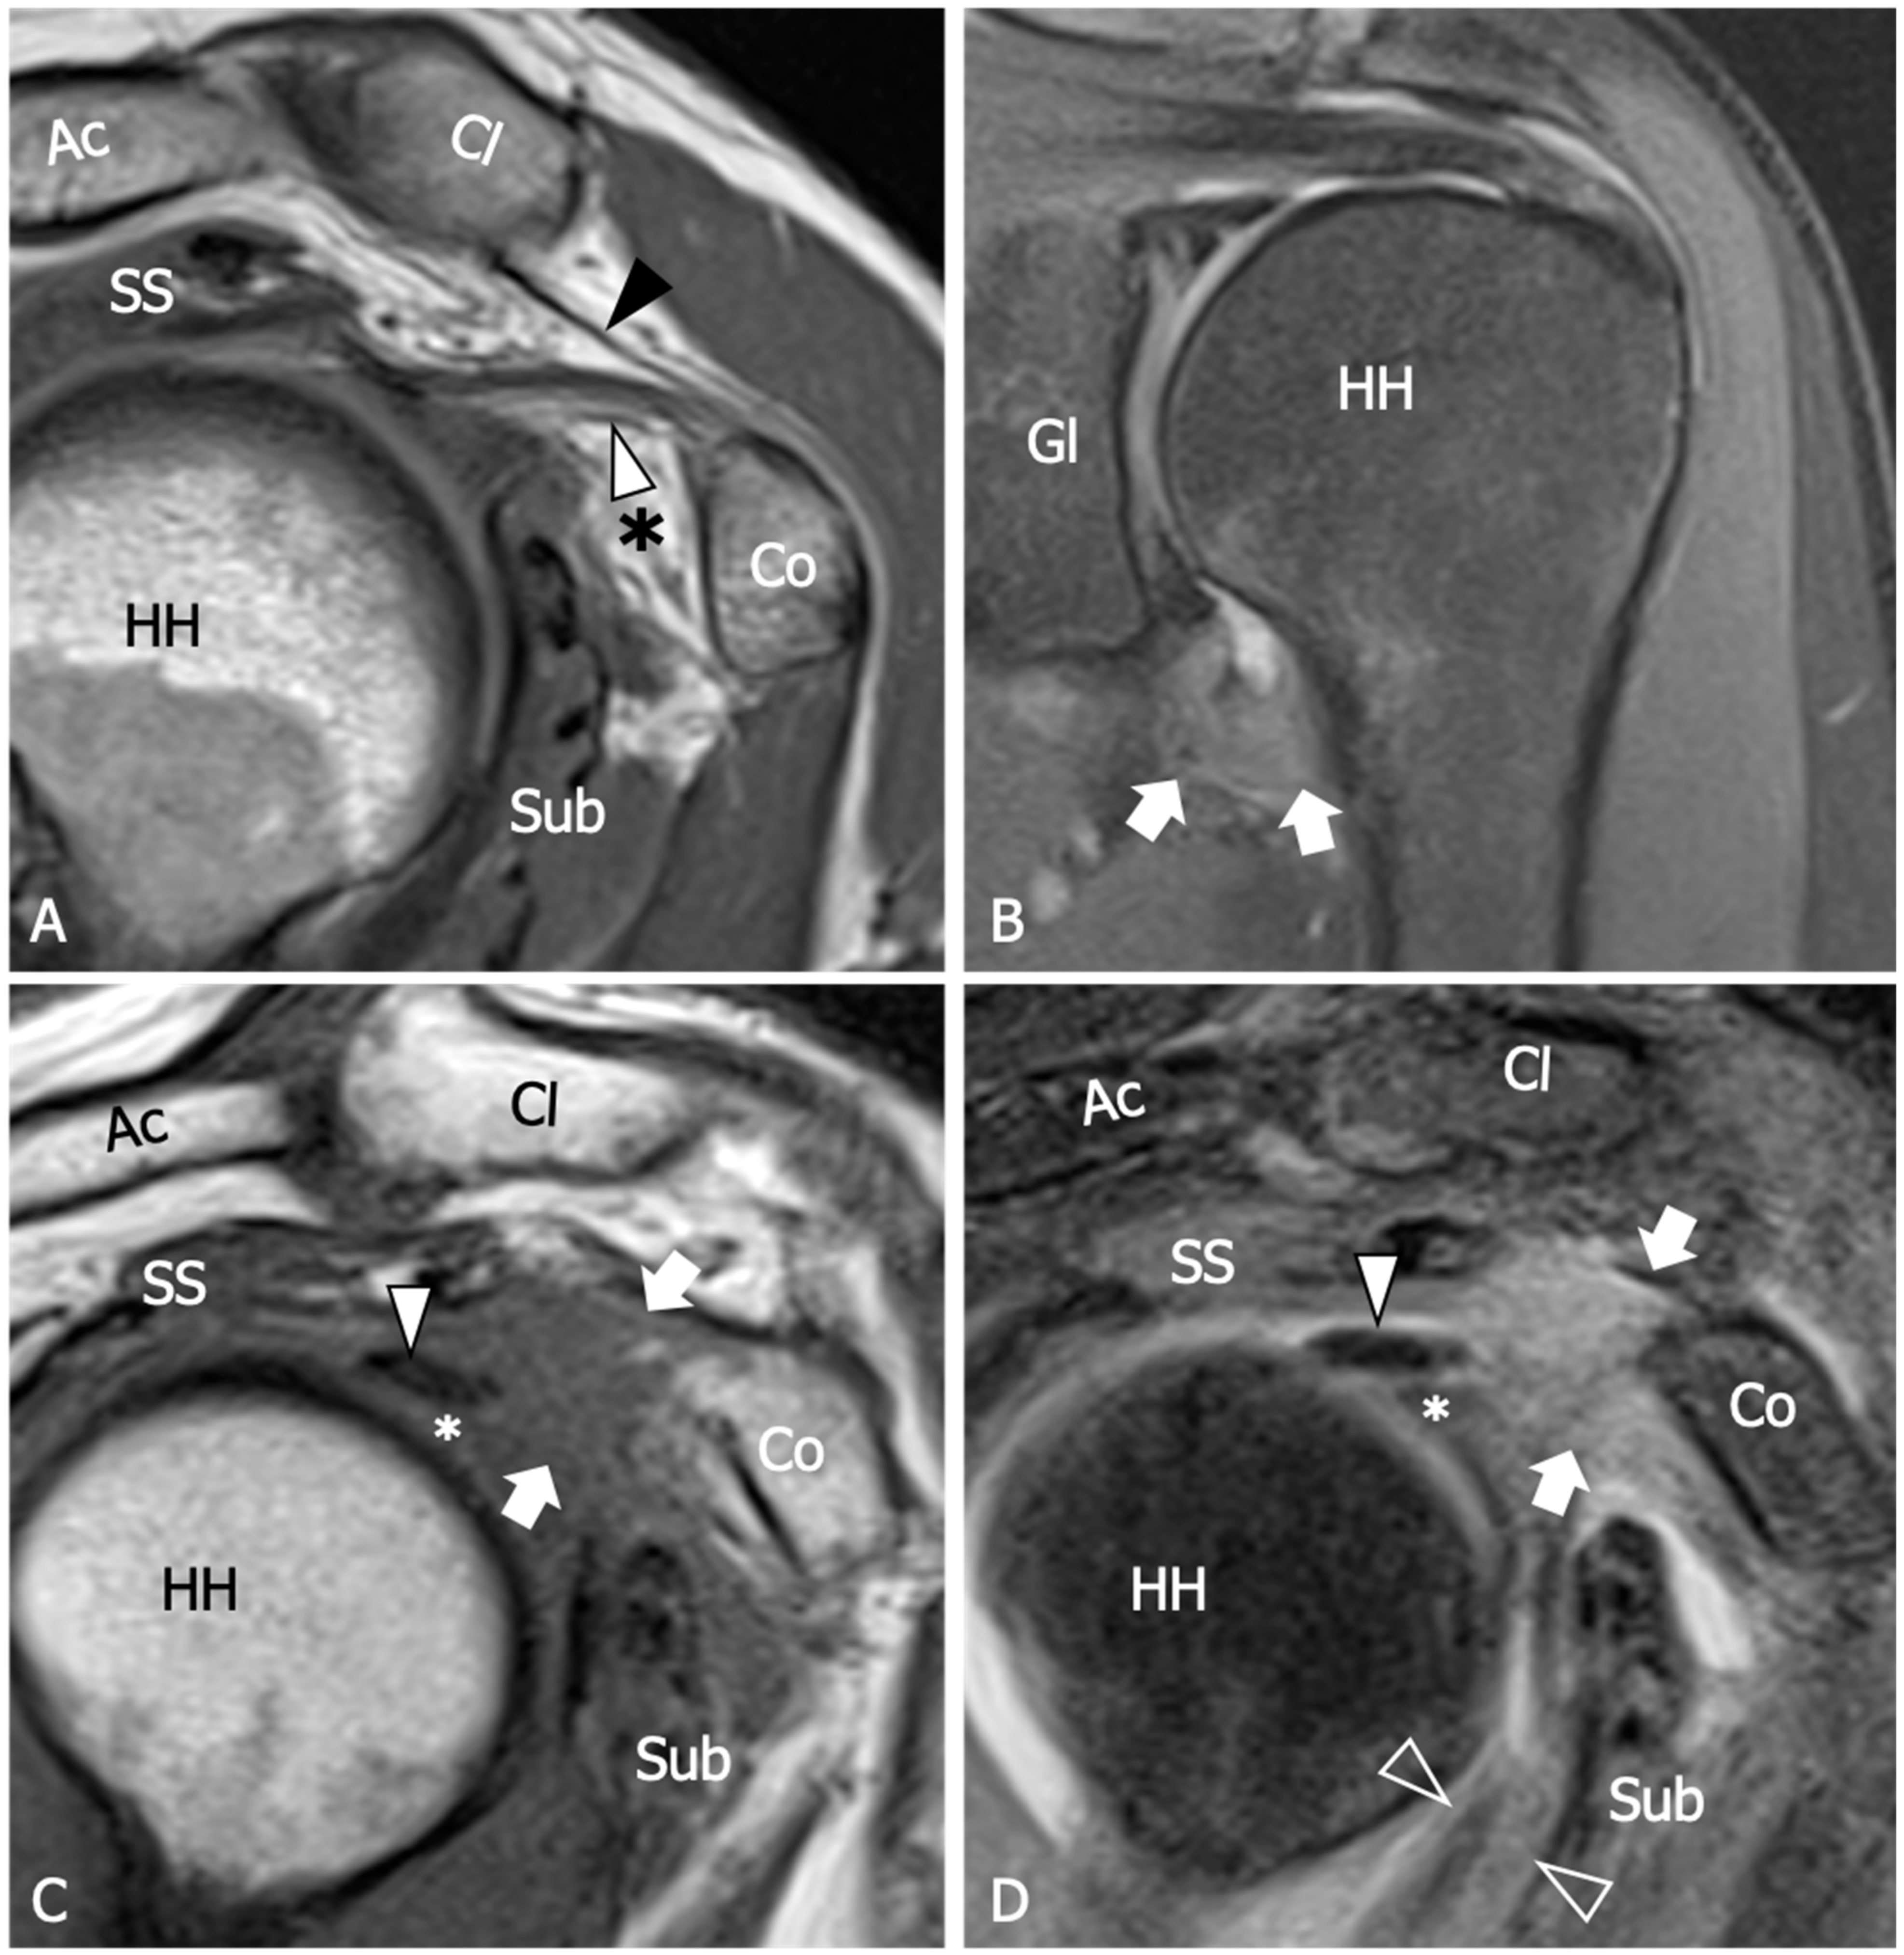

| Thickening of the coracohumeral ligament, fat obliteration of the rotator interval, hyperintensity and thickening of the inferior glenohumeral ligament, and contrast enhancement of the axillary joint capsule and the rotator interval are the most accurate signs of AC. The sensitivity and specificity of inferior glenohumeral thickening detected on conventional MRI are not significantly different from those detected on direct MR Arthrogram: consequently, the non-arthrogram MRI is recommended for AC diagnosis. | [53] |

| The rotator interval capsule thickness ≥7 mm has a specificity of 86% and a sensitivity of 64% for AC diagnosis. A coracohumeral ligament thickness ≥4 mm has high specificity (95%) but lower sensitivity (59%) for AC. Obliteration of the triangular fat pad inferior to the coracohumeral ligament has high specificity (100%) and poor sensitivity (32%). | [54] |

| Thickening of the rotator interval over 6 mm on sagittal oblique proton-density images may correlate with the patient’s range of rotational motion. An axillary recess capsule thickness of more than 4.5 mm measured on T1 oblique coronal images demonstrated the greatest diagnostic accuracy for AC diagnosis, with a sensitivity, specificity, and overall accuracy of 91%, 90%, and 90%, respectively. | [55] |

| Obliteration of the subcoracoid fat triangle has been more frequently observed in early stages of AC. Capsule thickness and hyperintensity on proton density sequence correlate with clinical stages. | [56] |

| Hyperintensity in the axillary pouch/inferior glenohumeral ligament complex on MRI using non-arthrography T2-weighted fat-suppressed sequences demonstrated high sensitivity (85.3–88.2%) and specificity (88.2%) and low variability among different observers with a kappa value of 0.85. | [57] |

| An axillary recess capsule thicker than 4 mm on T1 oblique coronal MR images suggests a diagnosis of AC with a sensitivity of 70% and a specificity of 95%. | [58] |

| A positive linear correlation is demonstrated between the grade of axillary recess capsule enhancement, the thickness of the joint capsule, and the intensity of pain in individuals with AC. No association was observed between the aforementioned parameters and the severity of range of motion limitation. | [59] |

| No differences in the accuracy of AC diagnosis emerged between conventional MRI and gadolinium-enhanced MRI despite the intravenous administration of contrast agent demonstrated to have some effects in increasing the reader’s confidence in measuring the joint capsule. | [60] |